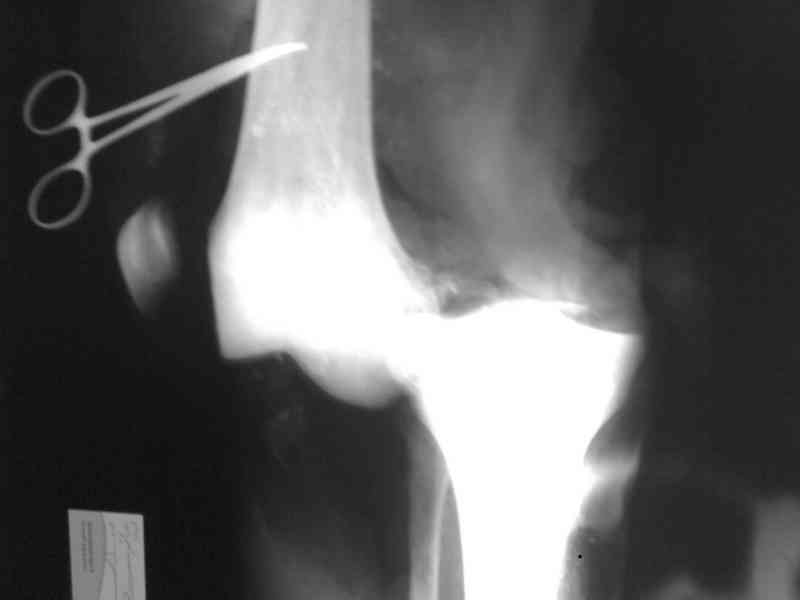

Bolnoi 27 let, DTP, Motorcycle trauma, postupil v kreane tiajelom sostoianii, osnovnia trauma- otkrity totalny vivih levogo kolennogo sustava s povrezdeniem malogo bersovogo nerva, tracionnoi povrezdenia podkolennoi arterii bez narushenia selostnost' sosuda, pomosh' okazanno v nujnum obmeme, kakoe ze mnenie uvazaemih kolleg naschet dalneshego vvedenia bolnogo? Castro

Uvajaemiy kollega! *Pomosh okazano v nujnom ob`eme*- kak ponyat? Vosstanovili krestoobraznih i bokovih svyazok? ili prosto vivih vpravili i fiksirovali AVF. sudya po R-snimkam nadkolennik nahoditsya visoko- znachit povrejdena i sobstvennaya svyazka, kotoraya ne ushita. Potom mojno sostavit plan lecheniya. S uvajeniem Abdurashid.

На ренгенограмме хорошая аппозиция костей коленного сустава, но надколенник находится подозрительно высоко, поэтому необходимо убедиться в отсутствии повреждения связки надколенника.

Наличие пульсации на конечностях еще не доказательство отсутствия интимальных повреждении сосудов, наблюдались вторичные осложнениия, поэтому важна консультация сосудистого специалиста.

Снимки прошлых публикации из моего Power point